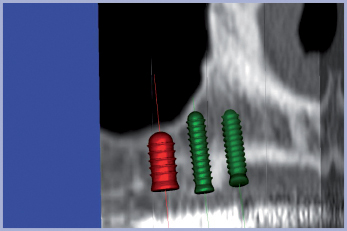

L’immagine TAC così ottenuta viene successivamente trasferita su supporto informatico CD leggibile con software dedicato Implant 3D (Media Lab srl – La Spezia) (figg. 2-6).

L’intero progetto implantologico, impostato ed elaborato su PC è inviato presso una struttura centralizzata dove, a mezzo di una tecnologia CAD/CAM, si trasforma la guida radiologica in guida chirurgica.

- Fig. 6